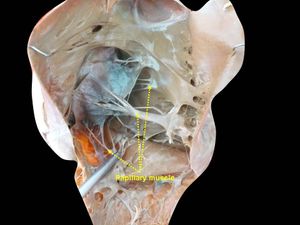

꼭지근은 심장의 좌심실과 우심실에 위치한 근육으로, 힘줄끈을 통해 방실판막에 연결되어 심실 수축 시 방실판막이 심방으로 밀려 올라가는 것을 방지하는 역할을 한다. 좌심실에는 두 개의 꼭지근이, 우심실에는 세 개의 꼭지근이 존재하며, 각 꼭지근은 특정 관상동맥으로부터 혈액을 공급받는다. 심근 경색이나 외상으로 인해 꼭지근이 파열되거나 기능 이상이 발생하면 승모판 역류를 악화시킬 수 있다.

심장에는 총 5개의 꼭지근이 있으며, 우심실에 3개, 좌심실에 2개가 존재한다.[16][17][2][8] 우심실의 꼭지근은 앞꼭지근, 뒤꼭지근, 사이막꼭지근(septal papillary muscleeng)으로 구성되며, 이들은 힘줄끈을 통해 삼첨판에 붙어 판막을 지지한다.[16][17][2][8] 좌심실의 꼭지근은 앞가쪽꼭지근(anterolateral papillary muscleeng)과 뒤안쪽꼭지근(posteromedial papillary muscleeng)으로 나뉘며, 역시 힘줄끈을 통해 승모판에 붙어 판막을 지지한다.[16][17][2][8]

우심실과 좌심실의 꼭지근은 모두 심실 수축기 직전에 수축을 시작하여 수축기 동안 긴장을 유지한다.[14][1][11] 이 긴장은 심실의 높은 압력으로 인해 방실판막이 심방 쪽으로 밀려나 탈출하는 것을 방지한다.[14][1][11] 이를 통해 심실 혈액이 심방으로 역류하는 것을 막는다.[14][1]